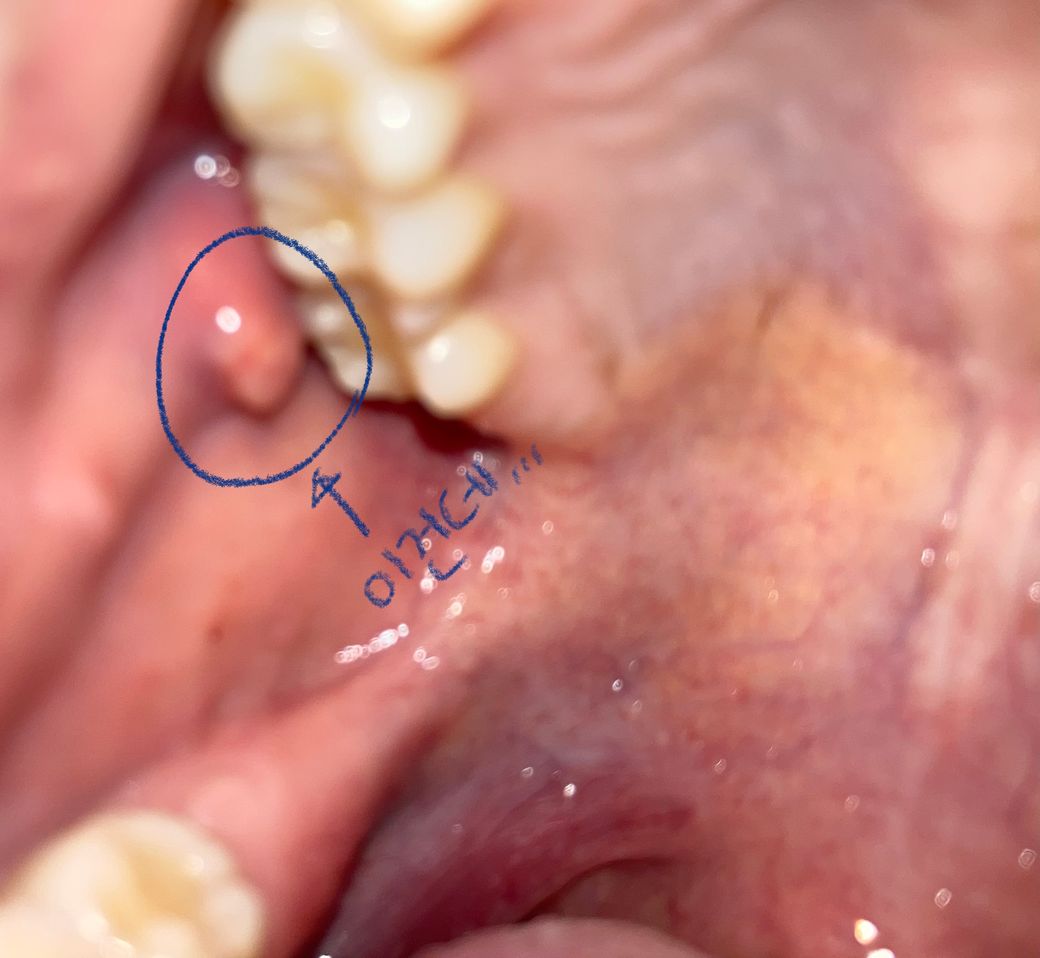

자고 일어나 보니까 입안이 다 헐어있고 오른쪽 볼 안쪽에 덩어리같은게 생겼는데 혀로 만지면 아파요...

이런적이 아예 처음이라.,, 게다가 오늘 1시간 정도만 잤거든요,,, 그전까진 안그랬는데,,. 갑자기 생겼는데 원래그 볼 안쪽에 있는 톡 튀어나온 부분에 생겼어요... 신경쓰이는데.. 병원에 간다든가 해야할까요? 사진이 잘 안찍히네요

• 1번 째 사진

사진의 병변은 점액종이나 섬유종을 감별할 필요가 있어 보입니다.